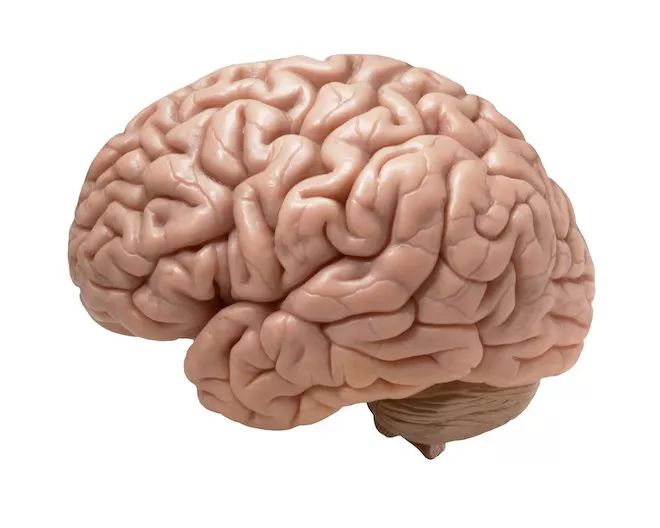

这一段会让大家明白为什么我平常喜欢把大脑画成这样一个可爱的样子:

因为写实的大脑非常的不可爱,让人起鸡皮疙瘩。

但是为了写这篇文章,我过去一个月在谷歌图片搜索上看了太多血淋淋的照片,所以各位读者也要看一些啦

当我们把外面这些东西都剥去后,剩下的就是这个:

这个看起来很荒唐的东西是宇宙里我们已知的最复杂的东西,重约三磅,功率约等于20瓦,相比之下,一个同等强大的计算机的功率约是2千4百万瓦。Tim Hanson教授把大脑称为“已知的信息密度最大、最有结构性,并且最能够自我构建的物质”

MIT教授Polina Anikeeva把大脑称为“能用勺子舀的布丁。”脑外科医生Ben Rapoport则更准确的把材质描述为“介于布丁和果冻之间”。Ben还解释说,如果把一个大脑放在桌上,重力会让它变形,变扁一点,就像个水母一样。我们的印象中脑不是这么湿软的,因为我们看到的脑常常悬浮在水中。

当你照镜子的时候,你看到自己的身体和脸,然后觉得那就是你,但其实你的肉体只是“你”所乘坐的一台机器。实际上,你就是这块布丁——希望你不要为此感到压抑。